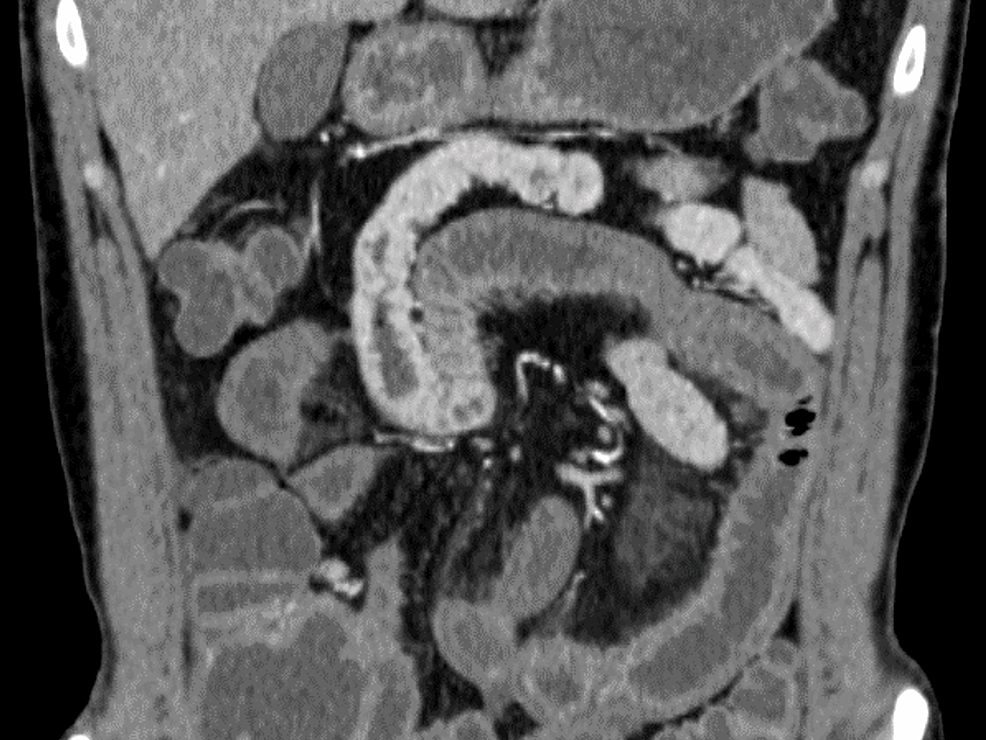

好酸球性肉芽腫の診断には、通常、腫瘍のマーカーを確認し、他の可能性を排除するための臨床検査および画像検査が含まれます。

X 線やCT スキャンなどの画像検査は、医師が成長を特定するのに役立つ場合があります。

ただし、他のいくつかの病気でも画像検査で同様の結果が得られる可能性があるため、医師は腫瘍を確認するために生検を行う必要があります。